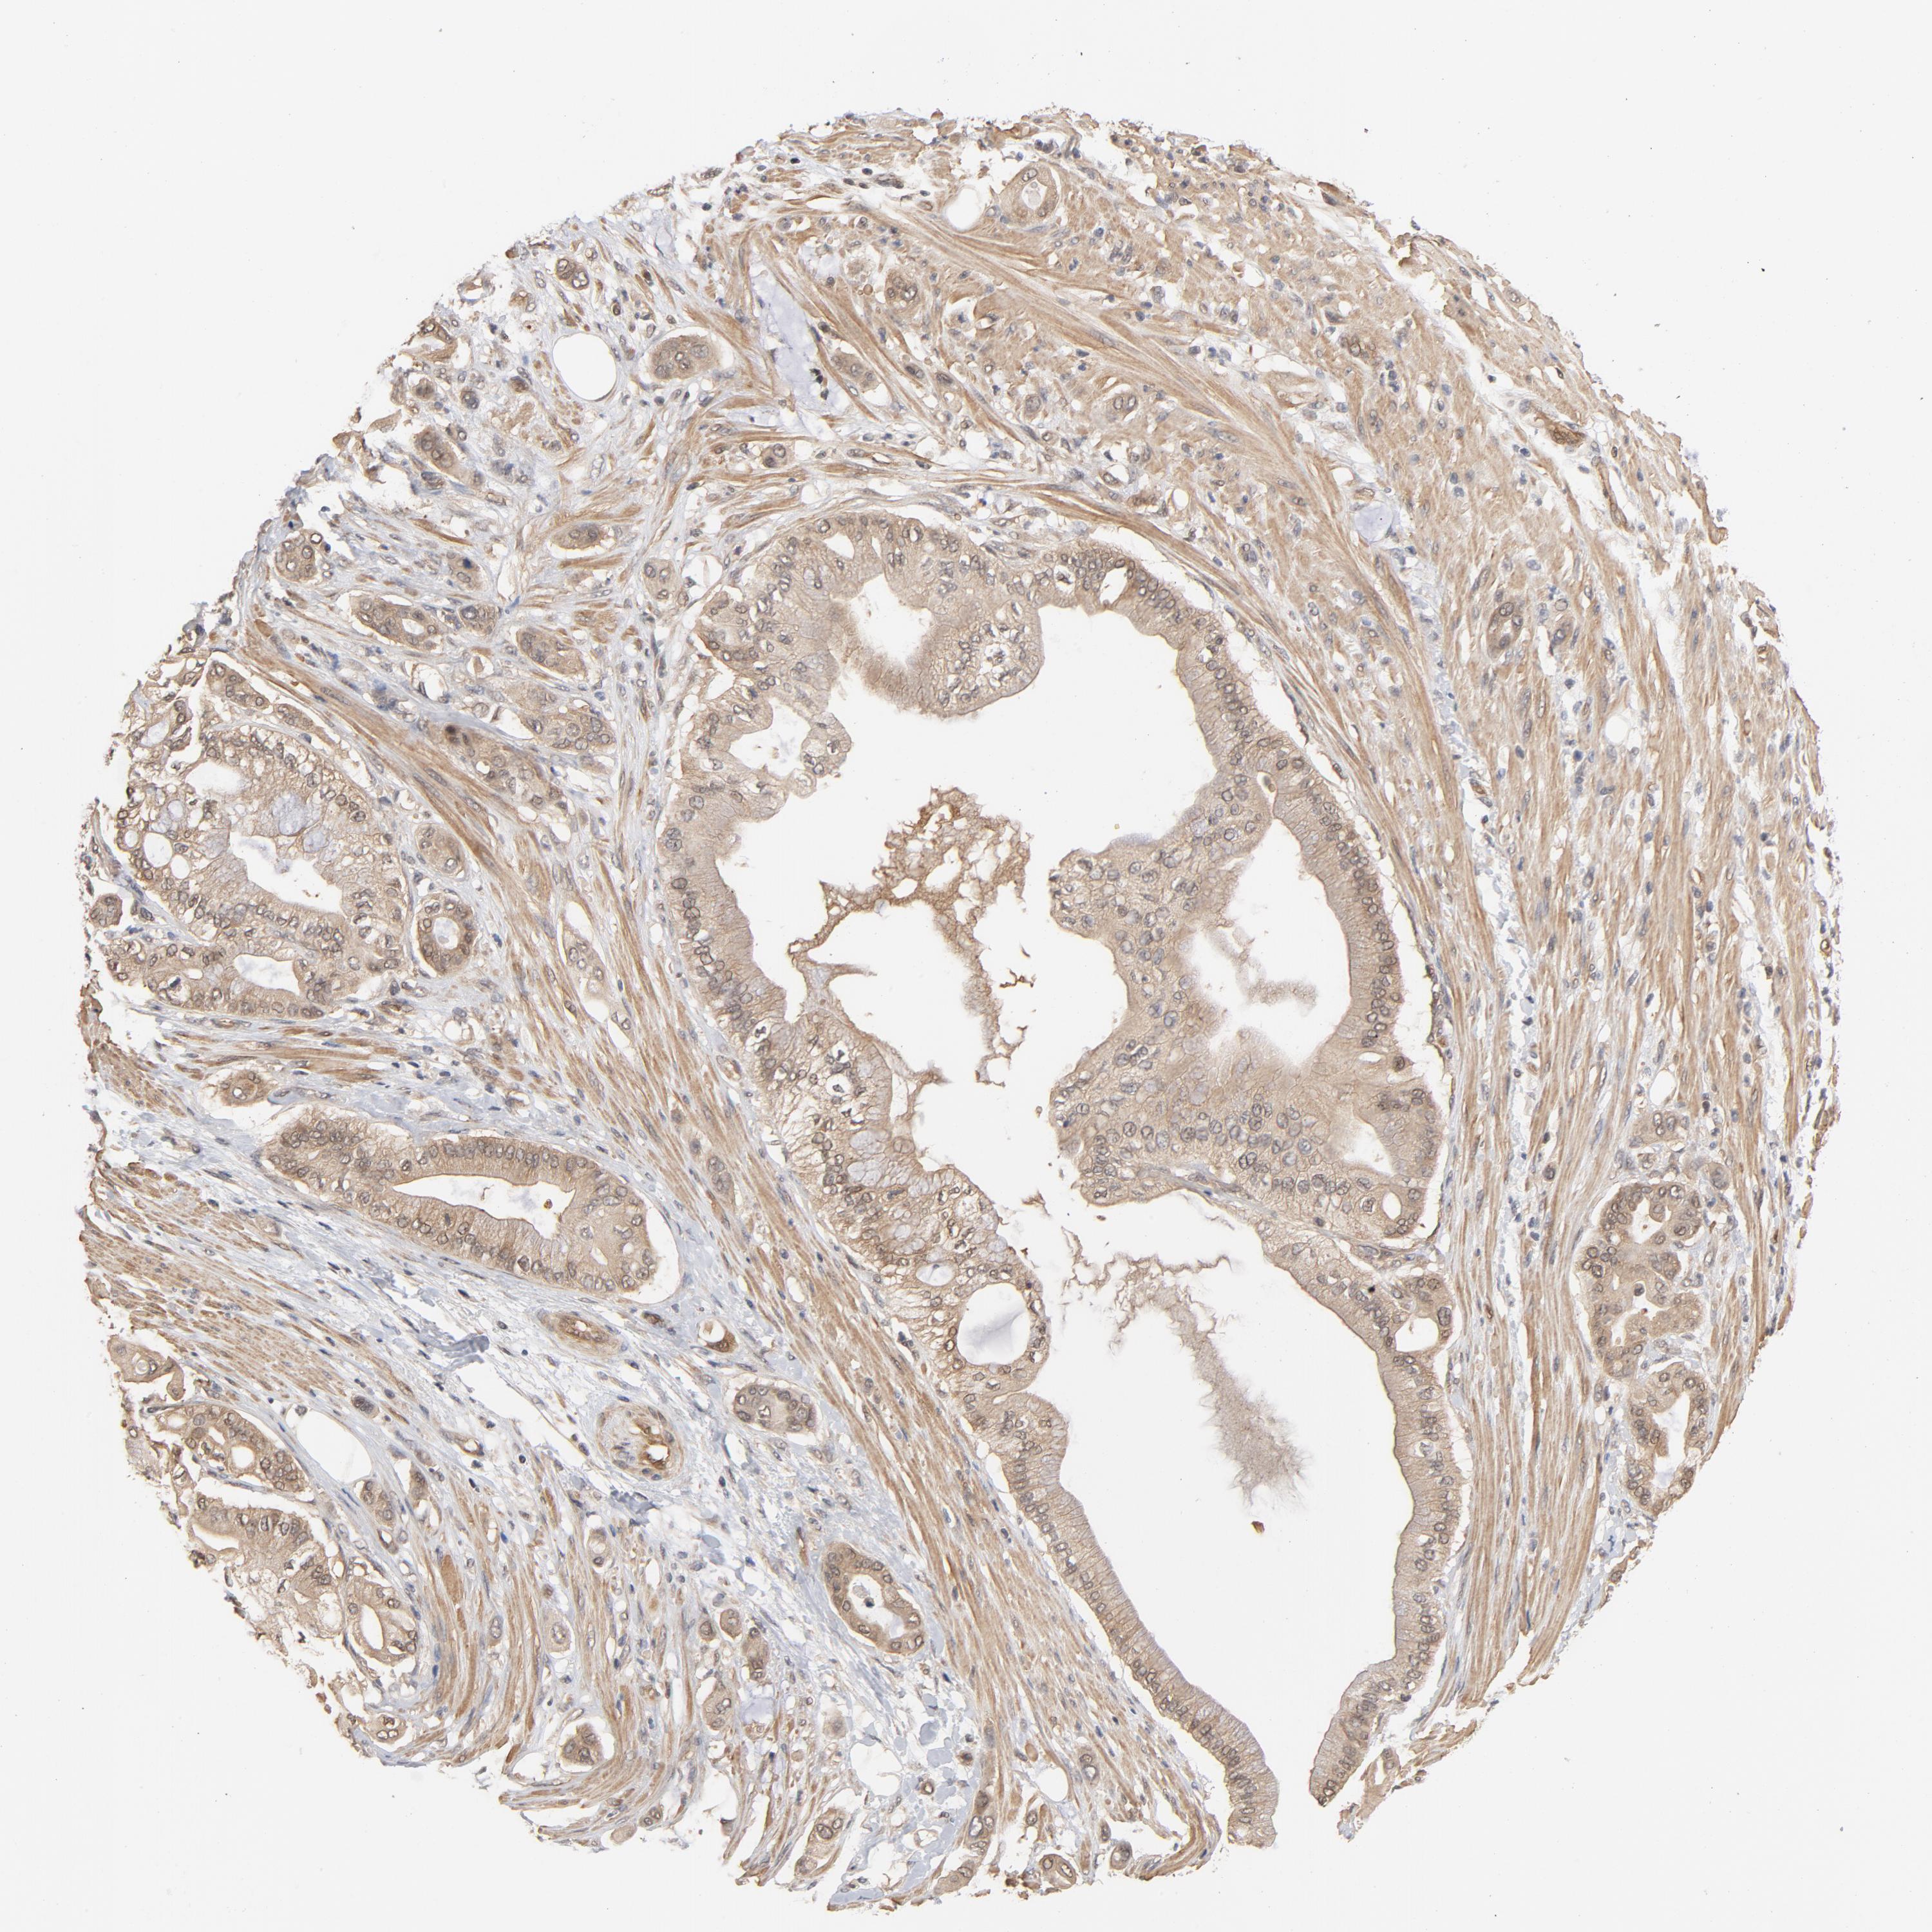

PANCREATIC CANCER - Protein expressioni

A mouse-over function shows sample information and annotation data. Click on an image to view it in a full screen mode. Samples can be filtered based on level of antibody staining by selecting one or several of the following categories: high, medium, low and not detected. The assay and annotation is described here.

Note that samples used for immunohistochemistry by the Human Protein Atlas do not correspond to samples in the TCGA dataset.

Antibody stainingi

Antibody staining in the annotated cell types in the current human tissue is reported as not detected, low, medium, or high, based on conventional immunohistochemistry profiling in selected tissues. This score is based on the combination of the staining intensity and fraction of stained cells.

Each image is clickable and will lead to virtual microscopy that enables deeper exploration of all samples and also displays staining intensity scores, fraction scores and subcellular localization as well as patient and tissue information for each sample.

Antibody HPA003928

Antibody CAB004214

Staining

High

Medium

Low

Not detected

Intensity

Strong

Moderate

Weak

Negative

Quantity

>75%

75%-25%

<25%

None

Location

Nuclear

Cytoplasmic/membranous

Cytoplasmic/membranous,nuclear

Adenocarcinoma, NOS

Adenocarcinoma, metastatic, NOS